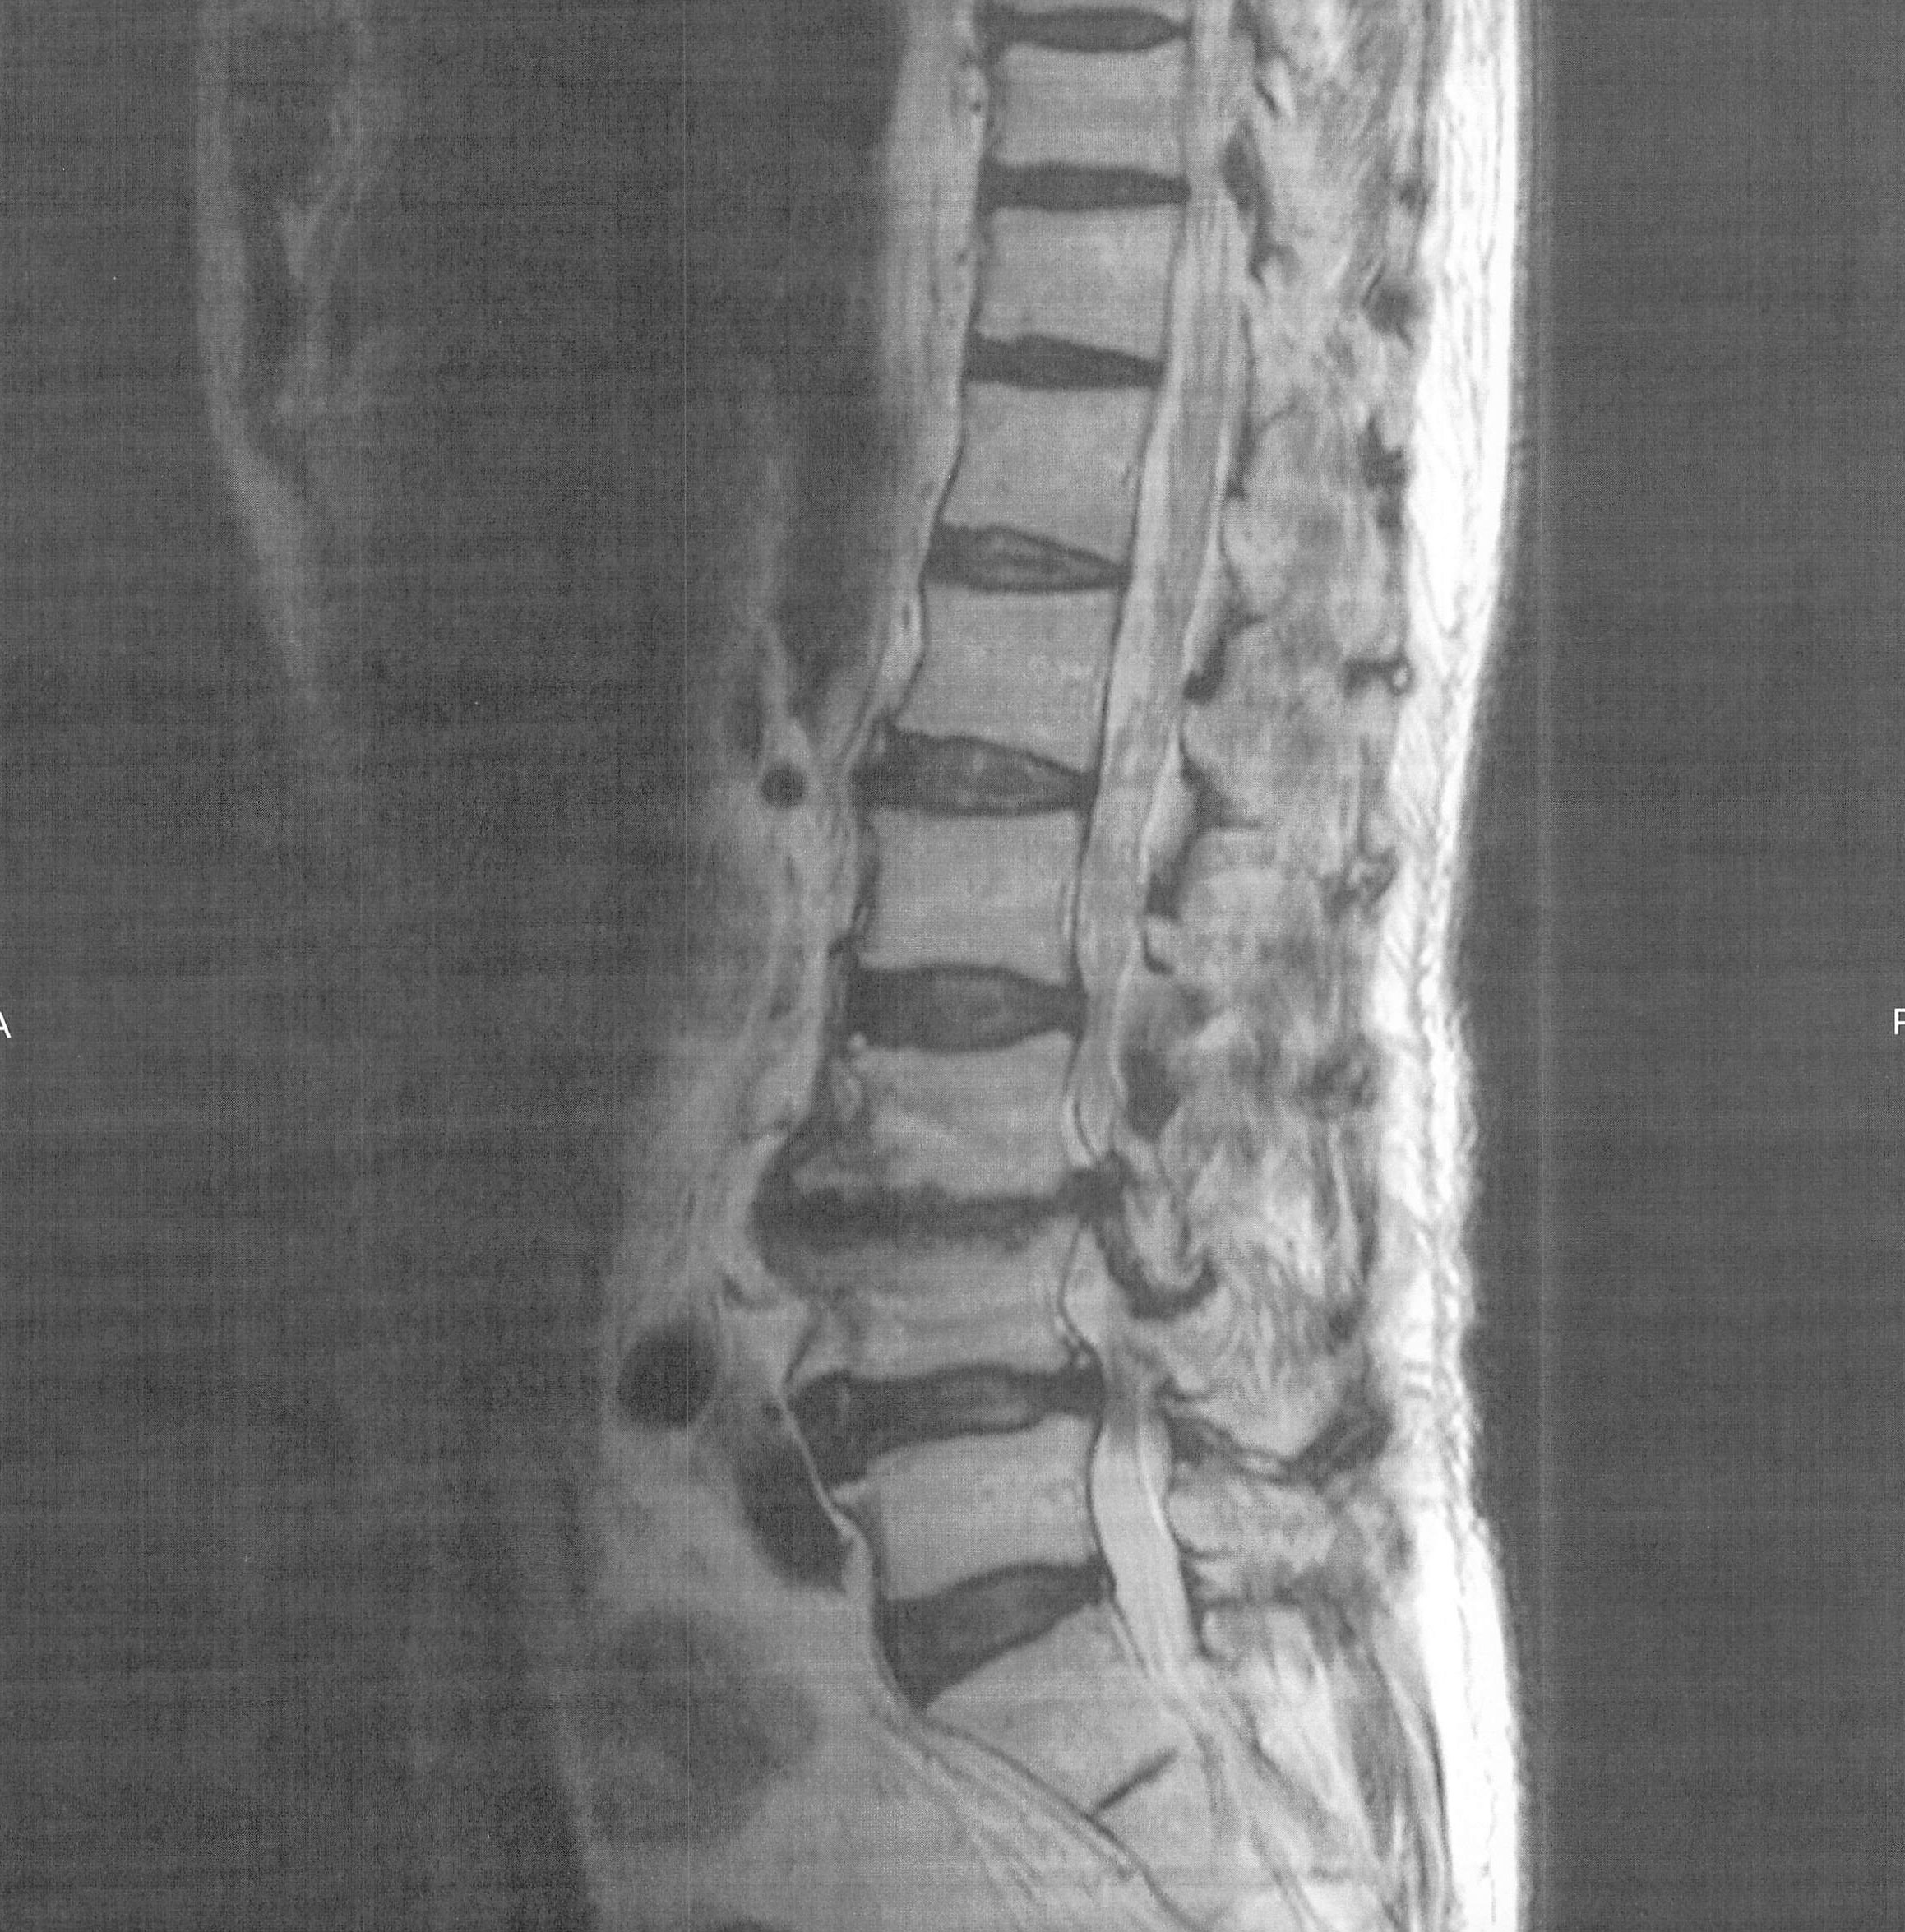

2013.2.14  13時30分よりY県立中央病院MRI検査を受ける。

検査後の診察で脊柱の2番から5番の間の3ケ処で、狭窄がおきておりその範囲は約10cmで、手術をする場合は約15cm切るとの事。

MRI検査の結果の画像はの通り。